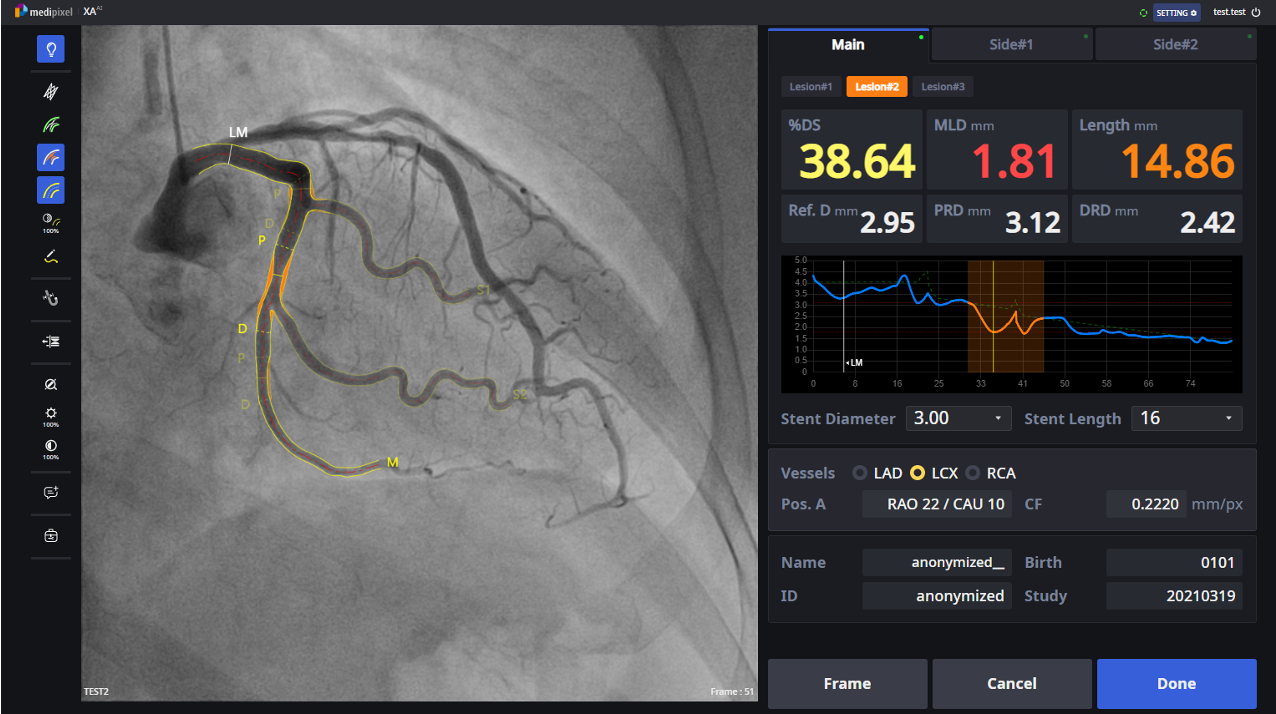

이 기술은 AI로 훈련된 알고리즘이 관상동맥 혈관을 분할해 주는 방법으로 1~2초 만에 혈관을 추출한 뒤 병변을 분석해 정량화하는 과정의 핵심 기술이다.

메디픽셀이 FDA 승인을 받은 제품도 이 기술을 기반으로 했다. 기존 외국 경쟁 제품들은 추가 수작업이 필요해 분석 시간이 길고 정확도가 떨어져 시술실에서 사용되지 못하는 반면, 메디픽셀 솔루션은 완전 자동화를 구현해 실시간 사용이 가능하도록 한 점이 특징이라고 전했다. 업계에서 기존의 심혈관 중재 시술의 진단과 치료 방법에서 혁신을 선도하고 있다는 평가를 받고 있다고 덧붙였다.